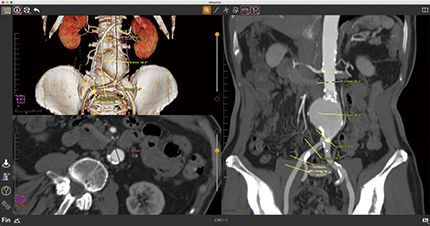

最新の画像診断装置からつむぎ出される膨大なデータの中には、体内の臓器や筋肉の働きが、想像を遥かに超える多様さ、詳細さで記述されています。このデータのどこをどう見たい、どう使いたいかは、臨床の現場で活躍するユーザーの皆さまそれぞれに少しずつ違います。医用画像解析アプリケーション「Attractive」は、その小さくて大切な「こだわり」に可能な限り柔軟に、確実に応えることで、日々の診断効率や精度の向上に貢献します。

簡単操作で曲線を展開表示、仮想内視鏡表示も搭載、マルチフェイズ・モダリティに対応、大動脈ステントサイジング機能も追加。